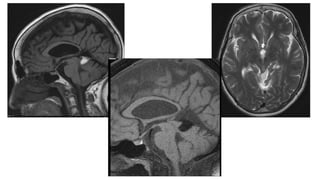

Vein of Galen aneurysmal malformation

• Common in childhood

• Commonest AV malformation diagnosed during antenatal screening

• Left to right shunt with high output cardiac failure

Imaging

• CTA

• MRI – signal void on T2

does not attenuate on flair

• MRA-Show dilated feeding and draining vessels

Image courtesy of Frank Gaillard radiopedia rID: 10512

• #51 Selected images from an MRI demonstrate a markedly enlarge flow void centrally, just above the pineal region, draining posteriorly to the sagittal sinus.

• #52 Large vein of Galen aneurysm flow void with significant local mass effect: compression of the aqueduct and 3rd ventricle anteriorly with secondary hydrocephalus. The inferior sagittal sinus is draining into the aneurysm directly and straight sinus draining out (as seen on T1W sagittal imaging)